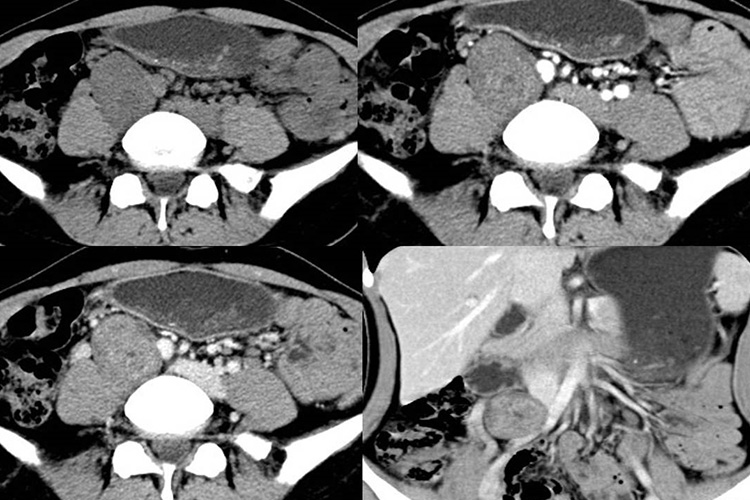

肌肉瘤的诊断需遵循临床表现、影像和病理学相结合,CT、MRI检查可发现相应部位的肿块及其周围浸润和转移情况,病理诊断是确诊的依据。